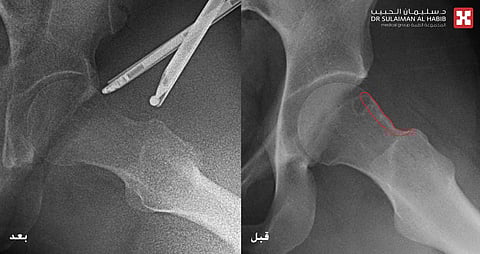

والذي أضاف أن المراجعة زارت مسبقاً عدداً من الأطباء لعلاج مشكلتها الصحية، ولكن دون جدوى، واصفين لها اتباع برامج علاج طبيعي وإعطائها أدوية مسكنة فقط، الأمر الذي فاقم من حدة الأعراض والآلام، مشيراً إلى أنه عند وصولها للعيادة، تم إخضاعها لفحوصات طبية دقيقة بالأشعة الرقمية السينية، والتي أوضحت وجود نتوء الكامة العظمي المسبب لمتلازمة الإصطدام الوركي الفخدي بزاوية (65) درجة، علماً بأن الزاوية الطبيعية تكون أقل من (55) درجة، موضحاً أن نتائج الفحوصات بالرنين المغناطيسي (M.R.I) بينت تهيج وإلتهاب شديد بالمفصل، واكتشاف ورم من النوع النادر في الجهة السفلية الخلفية لمفصل الورك، شارحاً أن مثل هذه الأنواع من الأورام تكون عبارة عن كيس بداخله خلايا تصبغيه ينتج منها افرازات زلالية داخل المفصل، ومع مرور الوقت تؤثر على الغضاريف المبطنة للمفصل والتي تؤدي للخشونة المبكرة.

وقال الدكتور خوجة أن الفريق الطبي عقب دراسته لكافة معطيات النتائج، إتخذ القرار بالتدخل الجراحي عبر إجراء عملية منظار للورك وعمل كحت لنتوء الكامة العظمي لمتلازمة الاصطدام الوركي وإزالة الورم الزلالي الصباغي، مفيداً بأن العملية استغرقت ساعة ونصف تحت التخدير العام، وتم فيها استخدام تقنيات المنظار وعمل تنظيف لمفصل الورك وإزالة التجمعات الدموية ، ومن ثم تحرير الورم من إلتصاقاته، وتقسيمه لأجزاء وإزالته بالكامل، كما تم إرسال عينه منه للمختبر، تبع ذلك عمل كي للشرايين المغذية للورم لمنع حدوث نزيف، كما ساهم إستخدام الإرشاد الاشعاعي في كحت النتوء العظمي، وبينت نتائج العينة أن الورم من نوع الخلايا العملاقة الزلالية الصباغية. مشيراً إلى أن جهود الفريق الطبي تكللت بالنجاح بفضل من الله، حيث نقلت المراجعة إلى جناح التنويم بعد العملية، وبدأت المشي باليوم الأول مع الإستعانة بالمشاية، وخرجت من المستشفى بعدها، مع إلزامها إتباع برنامج علاج طبيعي مكثف خاص لعمليات مناظير الورك.